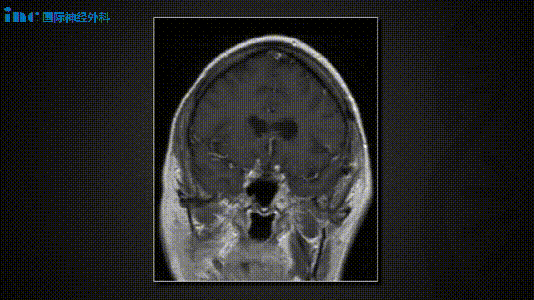

手术方案与体位的确定基于两处病变均引发症状,因此选择单一手术入路实施同期切除。采用中颅窝入路进行听力保留手术,并同期行岩骨前部切除以处理脑膜瘤。患者体位取侧卧位。中颅窝开颅、内听道磨除及岩骨前部切除操作中,沿颧颧弓根中心掀起4×4厘米骨瓣,识别棘孔后结扎脑膜中动脉。随后继续硬膜外解剖,定位弓状隆起及岩浅大神经(GSPN)。通过中颅窝入路磨开内听道,并保持硬脑膜完整性。为切除前庭神经鞘瘤,对内听道实施270°骨性开放。接着进行岩骨前部切除,磨除岩尖骨质。岩尖脑膜瘤切除步骤包括切开梅克尔腔表面硬脑膜,识别三叉神经根。在岩尖区域切开硬脑膜后,可见脑膜瘤向梅克尔腔延伸。完整切除脑膜瘤附着处硬脑膜,经硬膜开口分离肿瘤,使三叉神经根全程显露。前庭神经鞘瘤切除在脑膜瘤切除后进行,转向内听道处理前庭神经鞘瘤。术中持续监测听觉脑干诱发电位(ABR)。可见面神经位于肿瘤表面区域,通过充分磨除骨质实现肿瘤完整分离。在面神经表面缓慢分离肿瘤并行瘤内减容,清晰显示鞘瘤与神经界面。使用显微剥离器将肿瘤从其后方耳蜗神经区域抬起。切除鞘瘤后测试面神经功能,ABR反应保存完好。关颅步骤包括使用骨蜡封闭开放气房,以纤维蛋白胶复合脂肪组织填塞术腔。采用Medpor人工材料行颅骨成形术修复骨瓣,分层缝合头皮。术后影像与临床病程显示,影像学检查证实两处病变均获全切。患者术后出现一过性左侧外展神经麻痹,6周后完全恢复,听力保存完好。

手术方案与体位的选择鉴于两处病变均引起症状,决定通过单一手术入路完成同期切除。利用中颅窝入路实施听力保留手术,并同期进行岩骨前部切除以切除脑膜瘤。患者取侧卧位。中颅窝开颅、内听道磨除及岩骨前部切除过程中,沿颧颧弓根中心掀起4×4厘米骨瓣,识别棘孔并结扎脑膜中动脉。继续硬膜外解剖,定位弓状隆起及岩浅大神经(GSPN)。经中颅窝入路磨开内听道,维持硬脑膜完整性。为切除前庭神经鞘瘤,对内听道完成270°骨性开放。随后行岩骨前部切除,磨除岩尖骨质。岩尖脑膜瘤切除时,切开梅克尔腔表面硬脑膜,识别三叉神经根。在岩尖区域切开硬脑膜,可见脑膜瘤向梅克尔腔延伸。完整切除脑膜瘤附着处硬脑膜,经硬膜开口分离肿瘤,三叉神经根全程显露。前庭神经鞘瘤切除在脑膜瘤切除后开展,转向内听道切除前庭神经鞘瘤。术中持续监测听觉脑干诱发电位(ABR)。可见面神经位于肿瘤表面区域,通过充分磨除骨质实现肿瘤完整分离。在面神经表面缓慢分离肿瘤并行瘤内减容,清晰显示鞘瘤与神经界面。使用显微剥离器将肿瘤从其后方耳蜗神经区域抬起。切除鞘瘤后测试面神经功能,ABR反应保存完好。关颅操作包括使用骨蜡封闭开放气房,以纤维蛋白胶复合脂肪组织填塞术腔。采用Medpor人工材料行颅骨成形术修复骨瓣,分层缝合头皮。术后影像与临床病程中,影像学证实两处病变均获全切。患者术后出现一过性左侧外展神经麻痹,6周后完全恢复,听力保存完好。